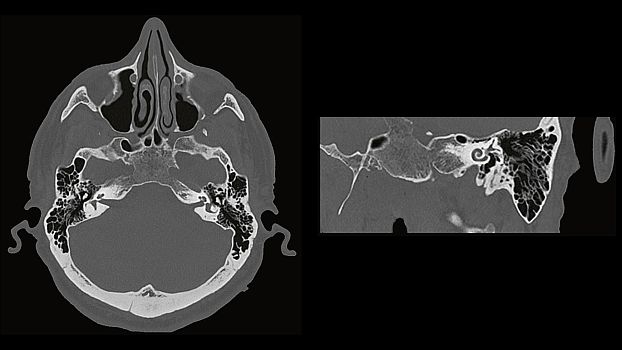

SOMATOM go.Up позволяет проводить высококачественные ангиографические исследования сосудов с хорошим контрастным усилением, субмиллиметровыми срезами и точной синхронизацией по времени.